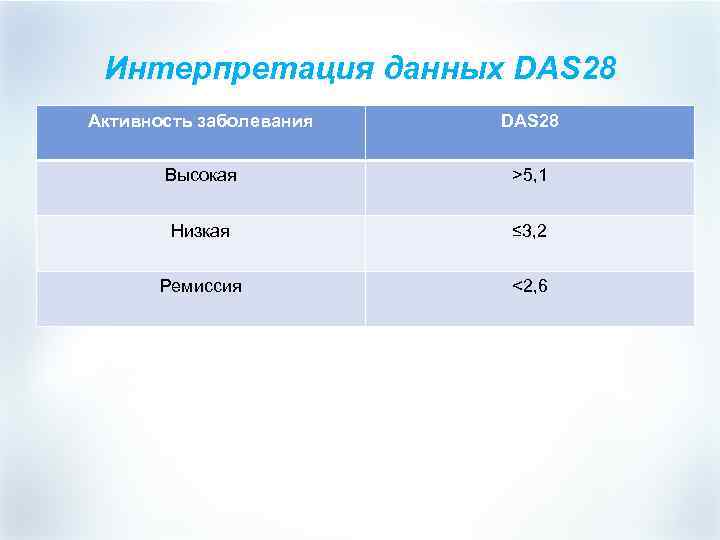

Интерпретация данных DAS 28 Активность заболевания DAS 28 Высокая >5, 1 Низкая ≤ 3, 2 Ремиссия <2, 6

Интерпретация данных DAS 28 Активность заболевания DAS 28 Высокая >5, 1 Низкая ≤ 3, 2 Ремиссия <2, 6